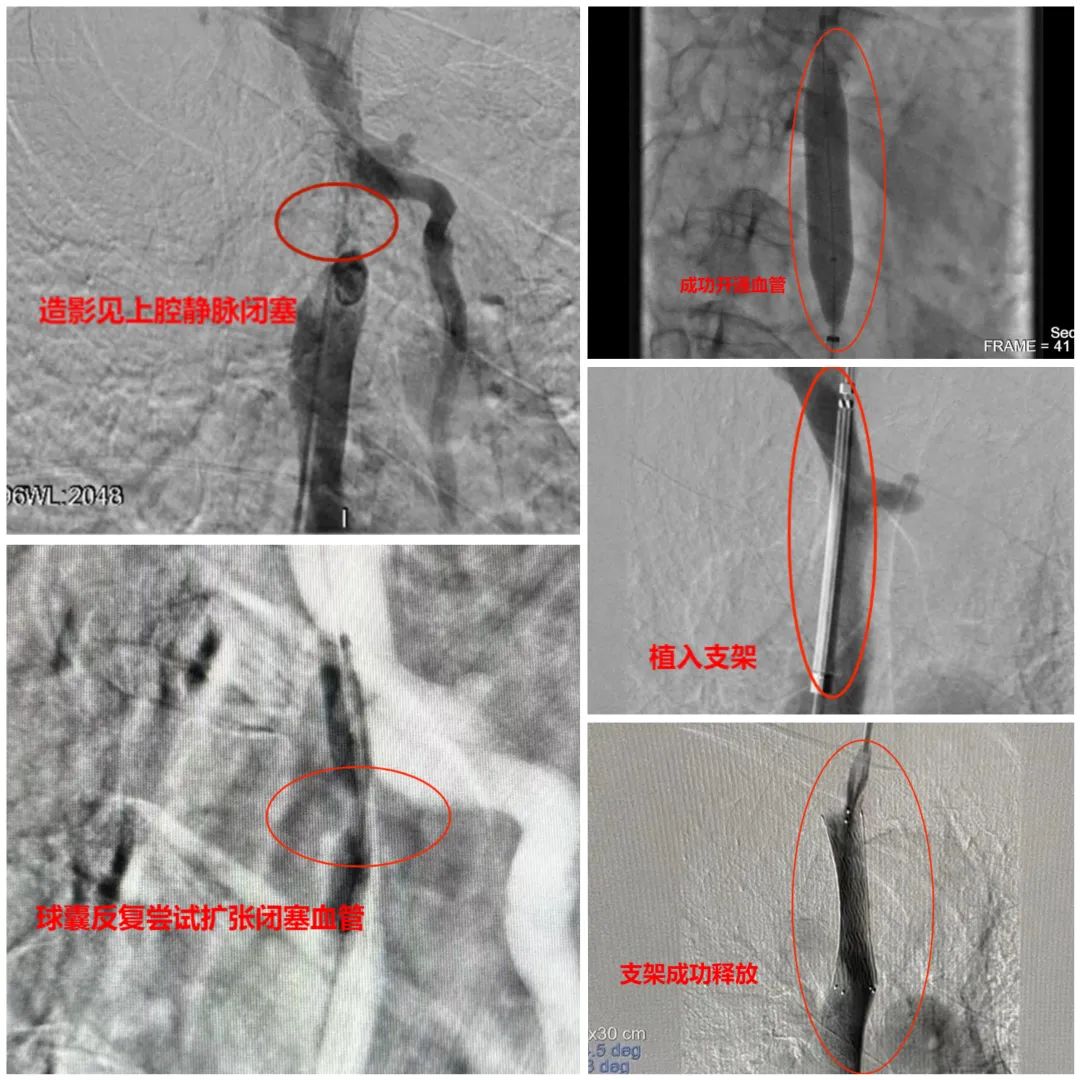

在于主任的指导下,侯军、姜海军副主任医师为老张做了【上腔静脉支架球囊扩张+支架植入术】。

术中,通过造影可见,老张的血管迂曲严重,走向分支错综复杂,导丝找到“堵点”后反复尝试探行,毫厘之间小心翼翼地变化角度位置,寻找“突破点”,终于扩开了约3厘米长的闭塞段,并成功植入支架,顺利地为血流钻出一条畅行通道。